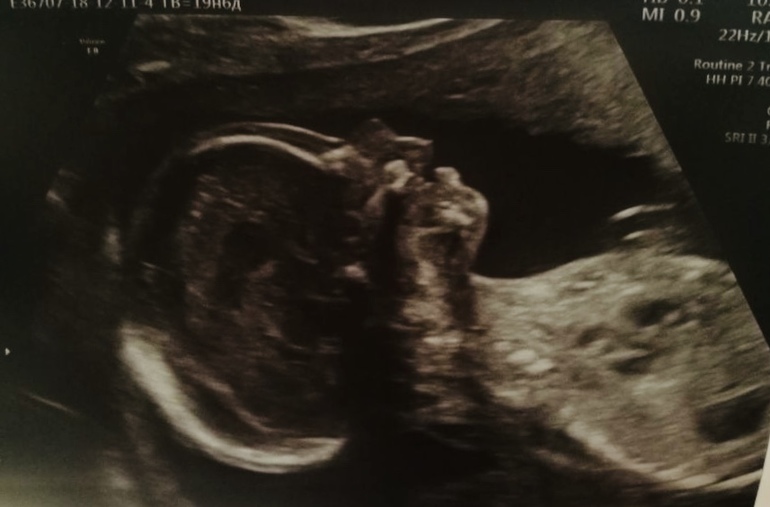

Позавчера были на втором скрининге. Вот этот человек внутри меня растёт, во что я до сих пор не могу поверить...

В общем, УЗИ хорошее, Крош весит 325 грамм и на несколько дней опережает срок, как и на первом скрининге. Похож на папу. Смотрю на этот профиль и прям ничего моего нет. Сказали умненький, что-то там в мозге хорошего размера😁 это в меня🙊

Низко расположена плацента - 25 мм от зева. Но врач сказала не переживать, поднимется. Никаких ограничений не озвучила. Я в целом спокойна, потому что на первом скрининге было как-то типа «хорион по передней стенке, доходит до внутреннего зева, не перекрывая его». То есть, если я правильно понимаю, на 2,5 см уже увеличилось расстояние.